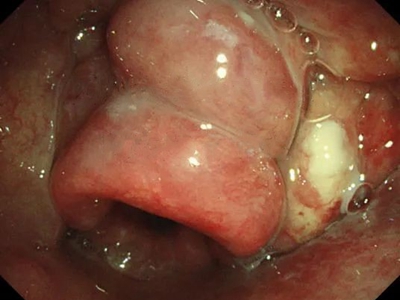

急性会厌炎起病急骤,有畏寒、发热、头痛等全身不适,多数患者体温在38-39℃。以剧烈的咽喉疼痛为主要症状,吞咽时加剧,重者饮水呛咳、流涎。喉镜下可见会厌舌面黏膜充血,高度肿胀水肿呈圆球状如卷曲香肠,肿胀可偏于一侧,偶见有黏膜溃疡。